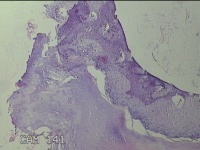

左拇指结节

性别

男

年龄

42岁

临床诊断

皮下结节

一般病史

发现左拇指结节8年余。

标本名称

大体所见

灰白粉红色组织1.3x0.8x0.3cm一块,表面带梭形皮肤1.3x1.1cm,皮下见结节0.8x0.5cm一个,切开结节呈实性,切面灰白粉红色,质中。